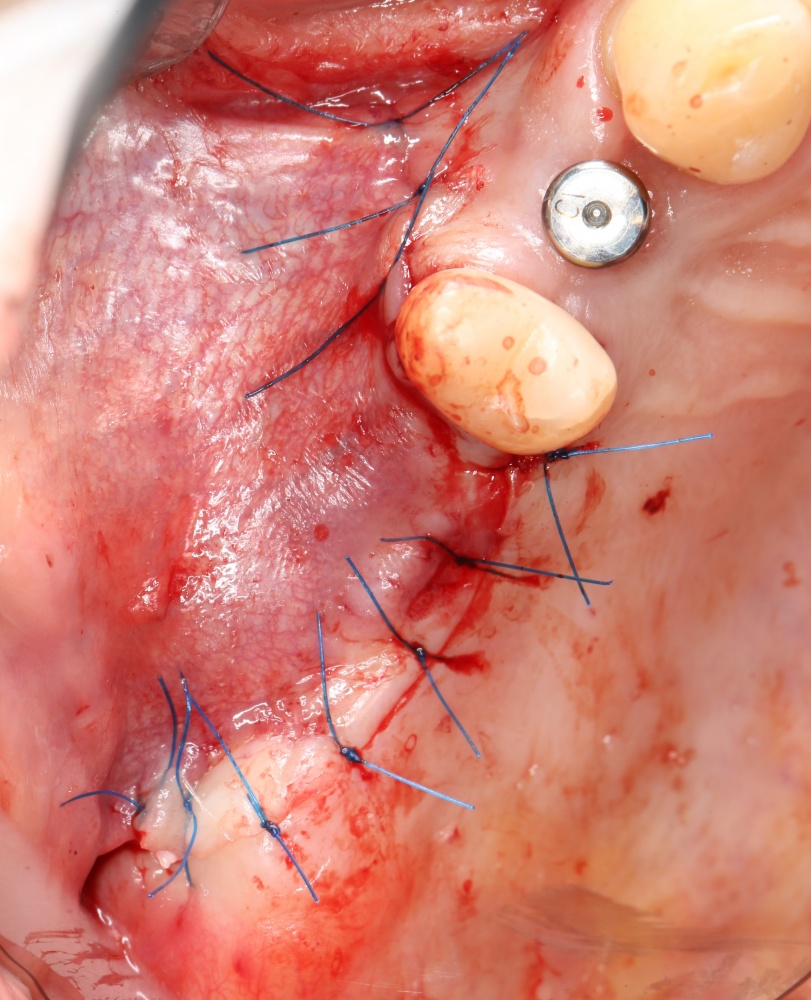

Далее, нам остается герметизировать послеоперационную рану тщательным и аккуратным наложением швов. Напомню, как разрезы, так и швы делаются в пределах кератинизированной слизистой оболочки. Это позволит уберечь рану от расхождения краев.

Послеоперационное ведение включает в себя периодические осмотры, антибактериальную и противовоспалительную терапию, некоторые правила послеоперационного режима на период 3-7 дней. Швы снимаются на 12-14 день, после чего ждем 3-4 месяца до момента регенерации костной ткани и интеграции имплантов.

Вот снимок сразу после операции: